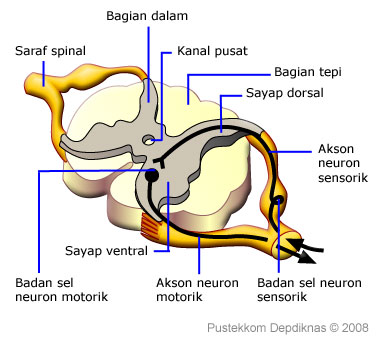

Sistem Saraf Pada Manusia Sistem Saraf Pusat Sistem

Sistem Saraf Pada Manusia Sistem Saraf Pusat Sistem

Fungsi Sumsum Tulang Belakang Mekanisme Penghantaran Impuls Pada Tulang Belakang

Fungsi Sumsum Tulang Belakang Mekanisme Penghantaran Impuls Pada Tulang Belakang